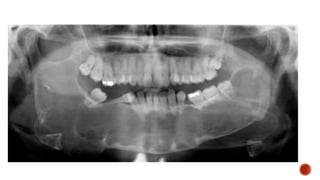

 Xray views for mandible

 AP and lateral radiographs of the skull show a well defined lytic lesion involving

the left ramus of the mandible causing scalloping of the medial margin with

associated soft tissue swelling.

MANDIBLE XRAY

 Axiolateral oblique

 The patient is seated upright

 Give true lateral position

 Slightly extend the neck

 Tilt the head towards the detector

 Central ray 25-30 degree cephalad

 The patient is stationary, while the x ray source and the film rotates.

 sitting/standing completely upright

 head immobilized and on a chin rest

 biting down on a radiolucent bite block

 tongue against the hard palate